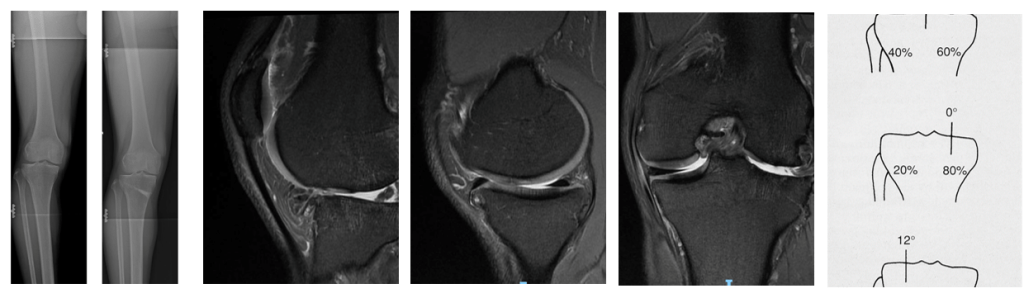

High Tibial Osteotomy (HTO) is a surgical procedure used to correct varus deformity of the knee or to manage recurrent instability after failed anterior cruciate ligament (ACL) reconstruction (ACLR). In particularly in cases with a steep posterior tibial slope (>12°) (Winkler et al., 2022).

By realigning the mechanical axis of the lower limb, HTO unloads the damaged medial compartment and can restore more physiological joint mechanics (Murray, Winkler, Shaikh, & Musahl, 2021). The procedure is most commonly performed as a medial opening-wedge osteotomy, where a controlled cut is made in the upper tibia and opened to the desired correction angle.

In select cases, particularly after multiple ACL failures, an HTO can reduce the posterior tibial slope to limit anterior tibial translation and graft stress (Winkler et al., 2022). For active individuals with unicompartmental degeneration or instability, HTO serves as a joint-preserving alternative to total knee arthroplasty (Parvizi et al., 2013).